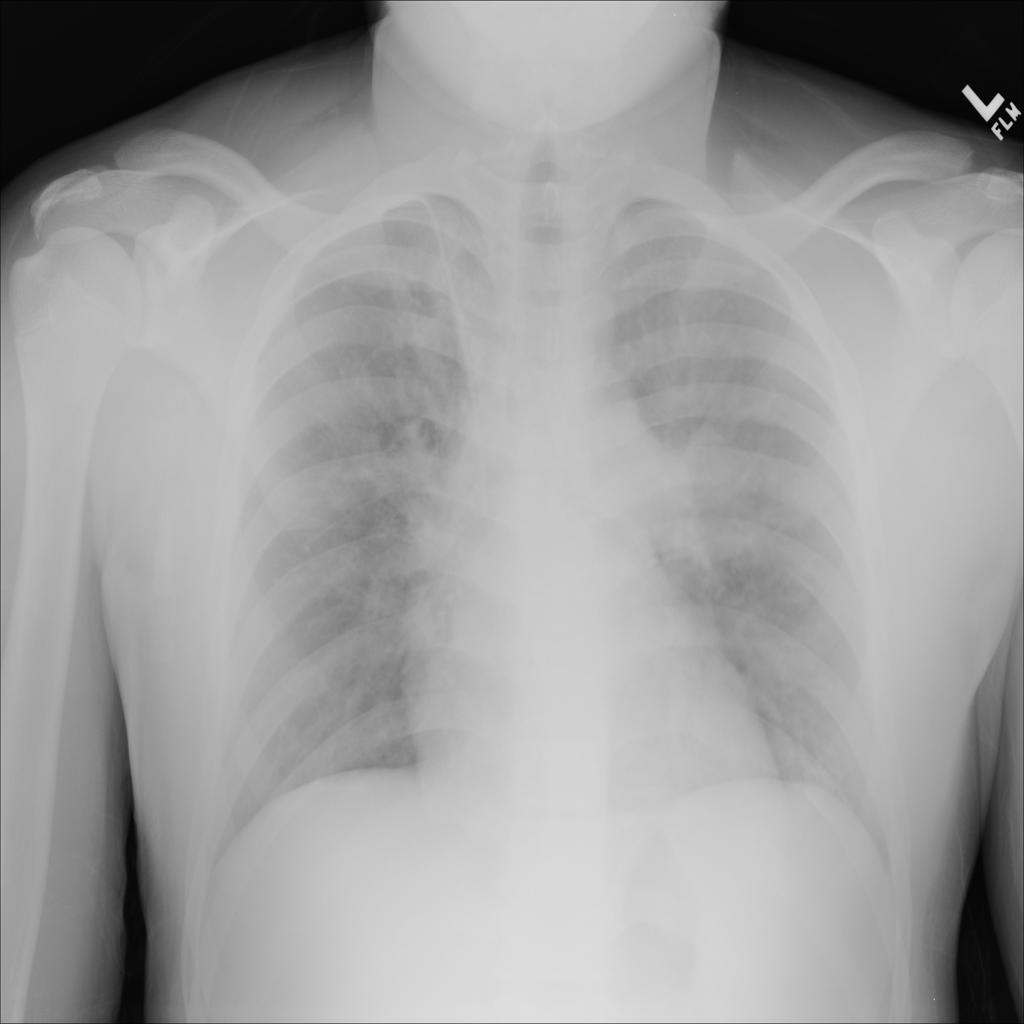

Consolidation

Consolidation refers to air-space filling that makes part of the lung appear denser on imaging.

Showing up to 90 reference images for Consolidation.

PAT-C1A7 · IMG-055Consolidation

PAT-C1A7 · IMG-055

AP